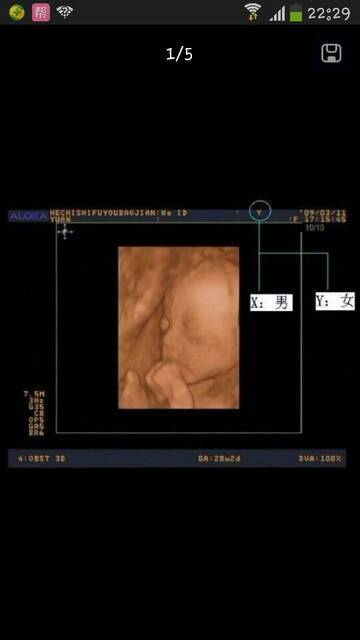

刚刚百度从B超单上说,能看男女,各位宝妈看看准不准,已生的宝妈最有发言权

刚刚百度从B超单上说,能看男女,各位宝妈看看准不准,已生的宝妈最有发言权。

一般情况怀孕后14周进行B超检查是可以的,一般情况是可以判断男女孩的,一般情况80%是比较可靠的,不过怀孕后进行男女孩鉴别是违法的,一般情况医院是不允许鉴别的,估计私人医院是可以做的,根据b超图像不能判断的

别相信没有依据的答案,B超单的数据都不准,只有做B超时医生说的才准确,但也不是百分之一百,只是相对的准确度高些